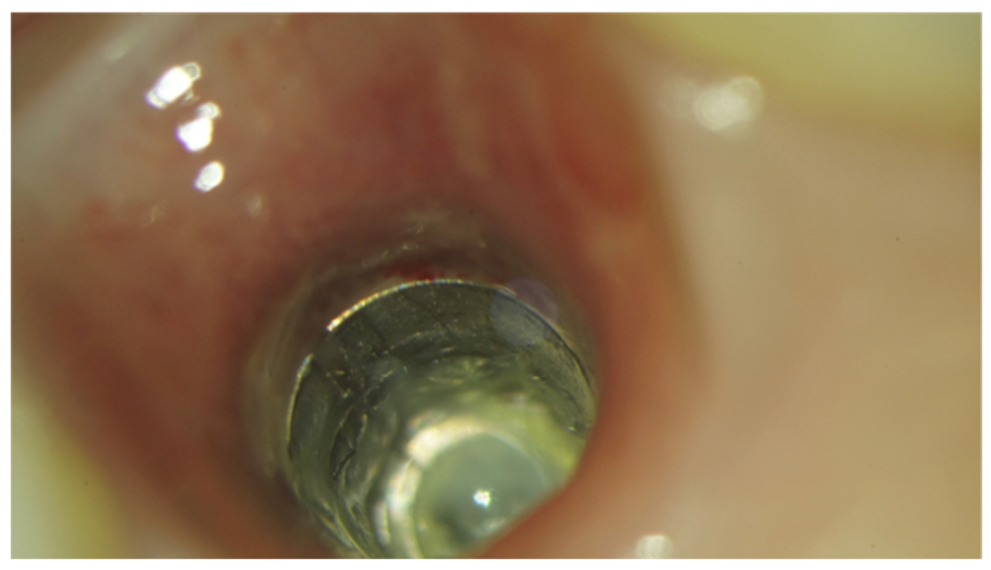

Implants fracture is an untreatable condition. There are several tools that may help clinician to remove the implant. However, fractured implant often presented damaged implant-abutment connection, hence, implant retrieval tools/kits (Figures 1–4) may not work. In cases implant is severely damaged and/or the residual osseointegration is very strong, such us in the mandible, the only possibility is to use a trephine burs (Figures 5–10).